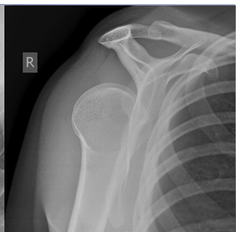

What is shown on this X-ray?